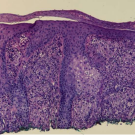

Catherine E. Lyons, BS, BA; Aaron D. Smith, BS; Nicole L. Edmonds, MD; Anya S. Chan; Vandana Nanda, MD; Margaret Noland, MD; Richard Hal Flowers, MD, BA

A 60-year-old woman presented for Mohs micrographic surgery to remove a suspected squamous cell carcinoma on the right nasal sidewall.